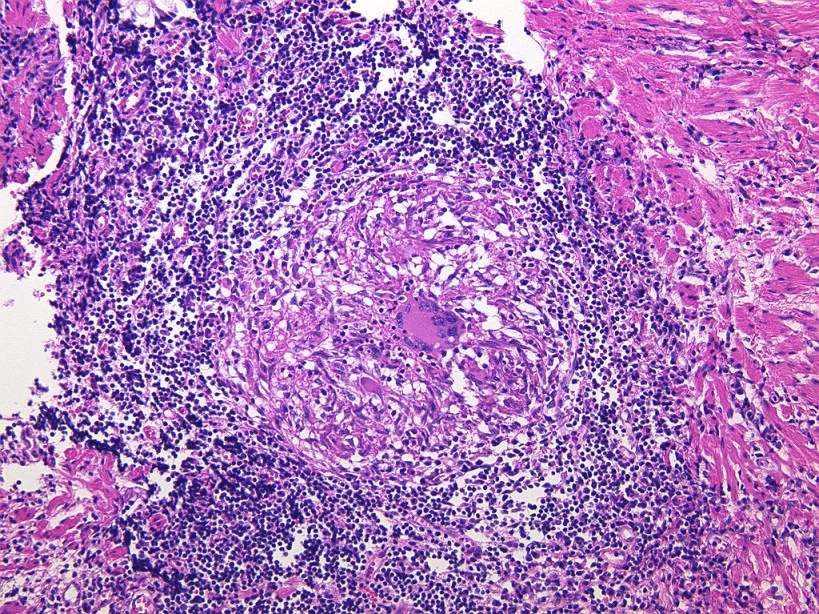

- クローン病

- 潰瘍性大腸炎

- 腸結核